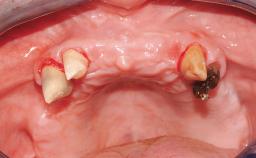

In September of 1995, a 64-year-old female patient presented to our clinic with a distally shortened arch in the left maxilla and the desire for a fixed rehabilitation. The patient’s medical history did not reveal any major issues, and she did not take any significant medication. She was a non-smoker and did not report any allergies.The patient wished to restore her chewing function on the left side, which was severely compromised due to the missing teeth 25, 26, and 27. The antagonistic lower teeth were present and in acceptable condition.